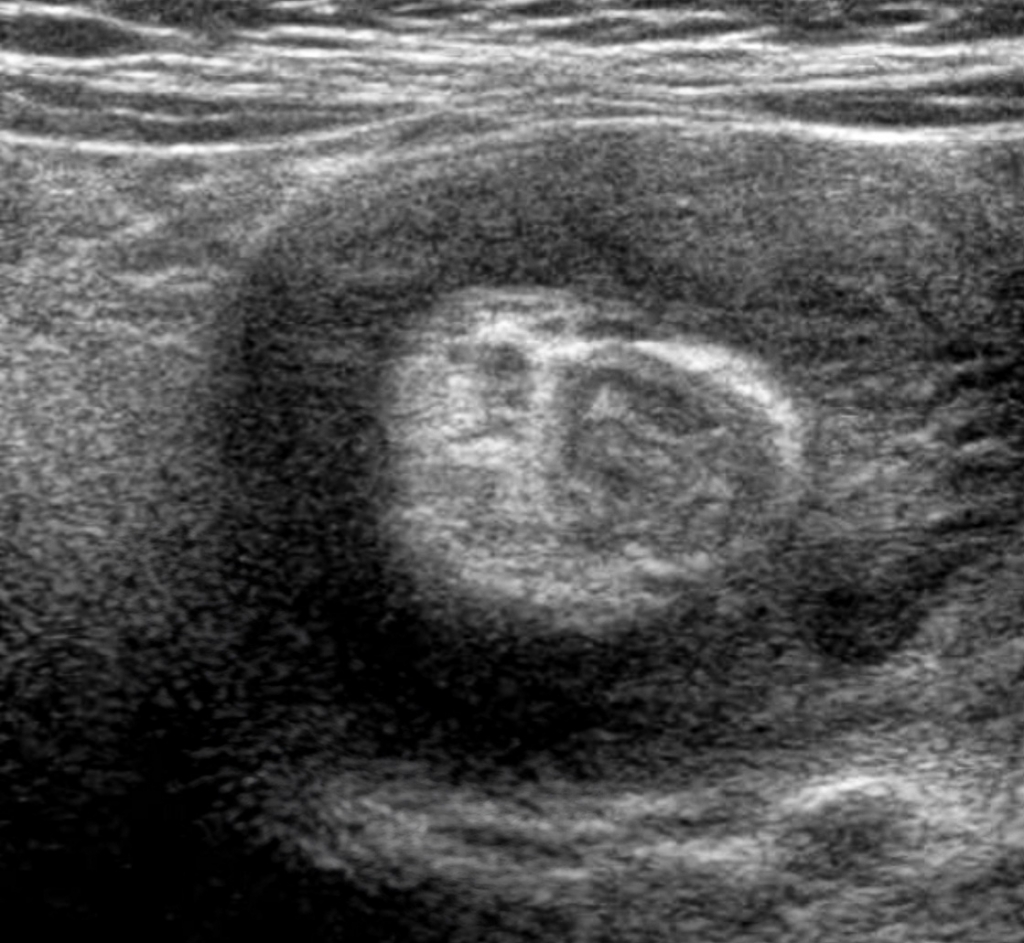

진단을 위해 가장 먼저 복부 엑스레이(X선) 촬영을 시행한다. 이를 통해 장관 내의 가스 분포를 확인하거나, 만져지는 종괴의 음영을 확인해 장중첩증을 의심할 수 있다. 이후, 복부 초음파로 '도넛 사인'과 같은 특징적인 소견을 통해 정확한 진단을 할 수 있는데, 장이 말려 들어가 겹친 모양의 단면이 마치 도넛 모양으로 보이기 때문이다.